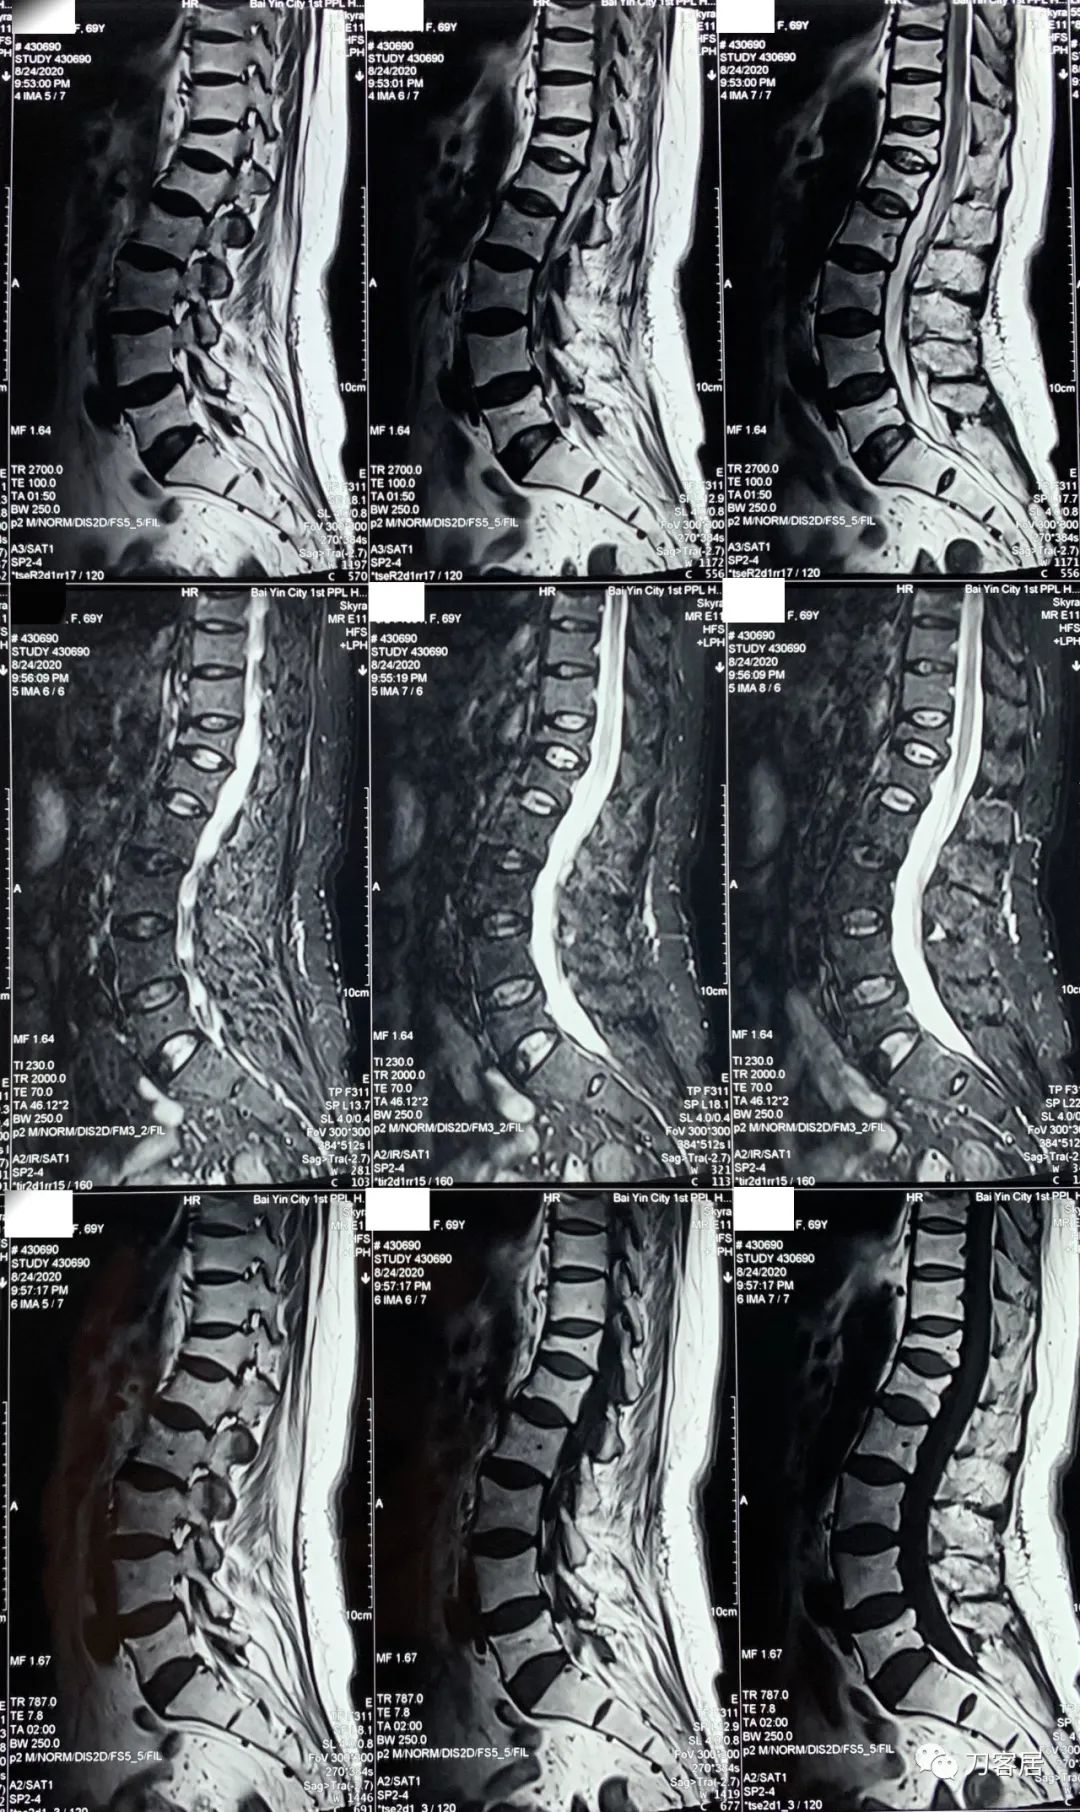

自带影像学资料提示胸椎,腰椎多发脊柱压缩性骨折。

诊断 : 重度骨质疏松症,胸椎、腰椎多发椎体压缩性骨折

图05-20200824白银市第一人民医院胸椎MRI

图06-20200824白银市第一人民医院腰椎MRI